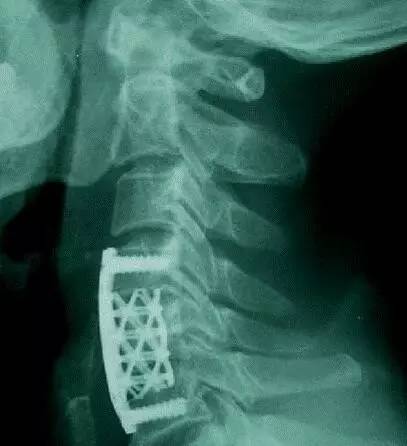

用来替换4节颈椎的3D打印内植物(是不是跟想象中的完全不一样,做成这样是有原因的,后文会告诉你)。该内植物通过两端的接头直接固定在第一节和第六节椎骨上。它的力学强度和与上下椎骨的接触面积,都明显大于传统的钛网。一段时间后,这个具备人体生理曲度的「海绵状」微孔钛合金3D打印内植物会被新生的骨组织充满(见下图),并被各种软组织包被。(北医三院供图)

在技术相对成熟的今天,定制3D打印内植物的过程并不复杂。首先给病人做CT扫描获取患者的颈椎数据,并用专业的软件把CT扫描的数据转换成3D打印的数据,然后就可以打印出患者的颈椎模型。医务人员再根据这个颈椎模型来设计内植物的大小,曲度和形态,然后把数据输入到相关的设备里面,只需开动机器打印就行了。按照目前的设备,打印这个替代4节椎骨的内植物大概需要13个小时左右。

奇点一直以为定制化3D打印椎骨跟人体的椎骨一模一样,然而并不是,而且完全不一样。后来奇点了解到,定制化3D打印椎骨之所以跟椎骨不一样,主要是考虑到实用性。由于颈椎中布满神经、血管和脊髓,所以为了便于手术中操作方便,在满足力学强度的前提下,就要把植入物设计的相对小一些。这样对患者的创伤也较小,更有利于患者快速恢复。

这个定制化3D打印椎骨最大的难点和亮点是通体「海绵状」的微孔结构。这就意味着整个内植物都是由微孔组成的。这样设计的目的主要是为了让人的骨头可以直接长到微孔里面,和这个内植物实现融合(7)。这也是跟钛网最主要的区别。